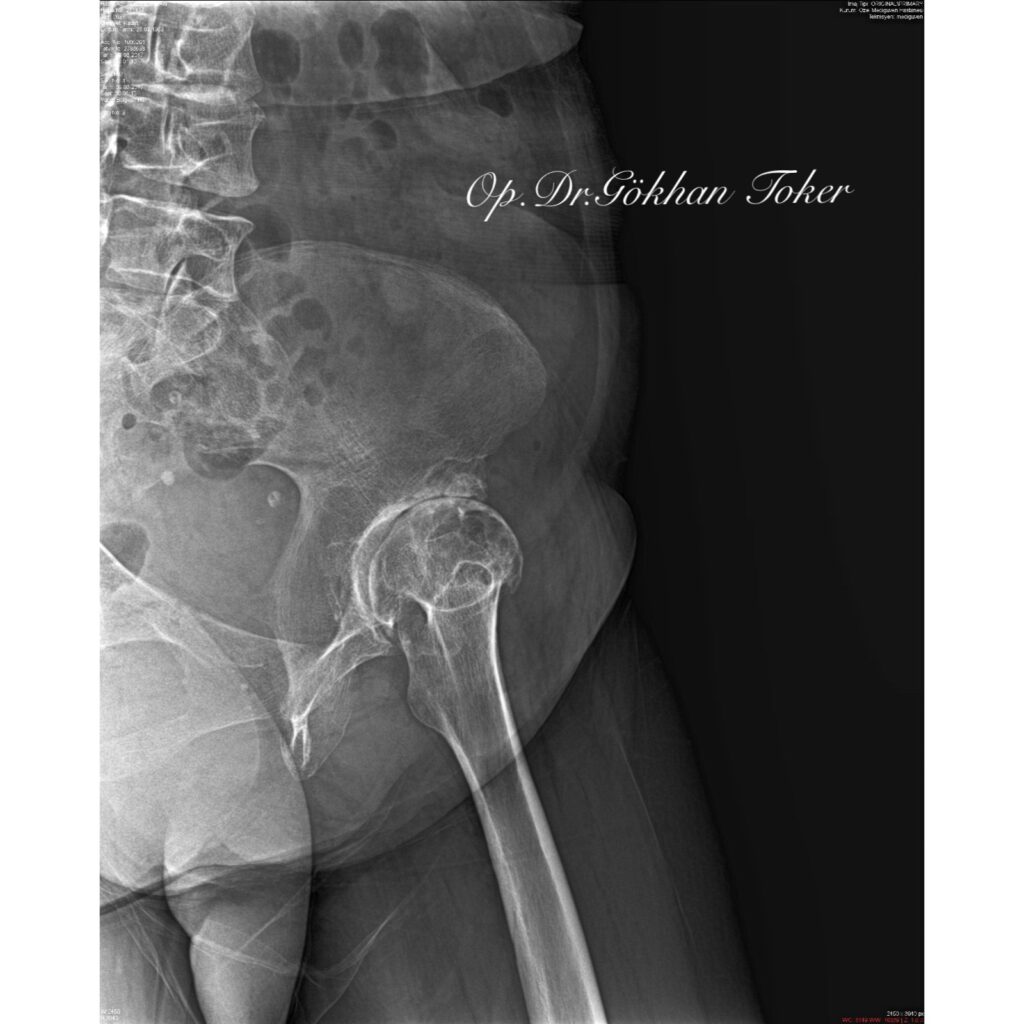

V.K.